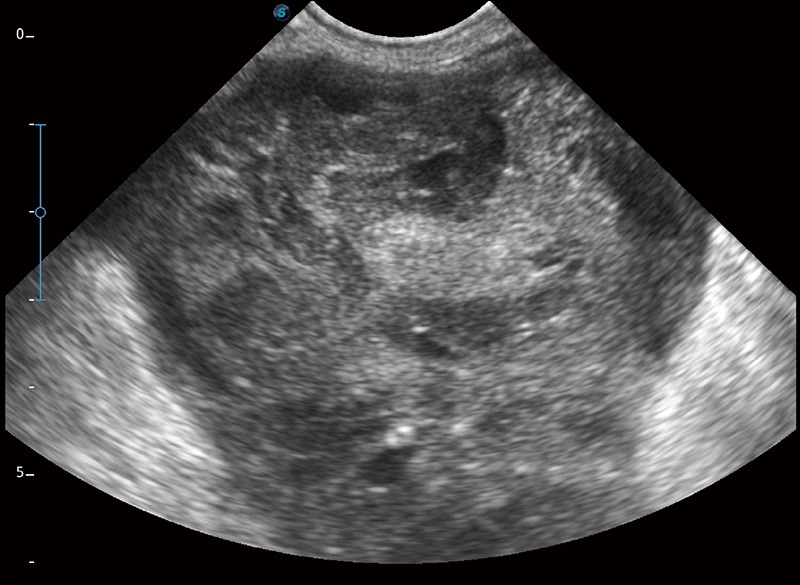

精致轻巧 性能迅捷

α1卓越的图像质量和便捷的工作流程,使每位宠物医生都能轻松扫查。其全面的兽用应用功能和紧凑型的结构设计,可以满足动物检查的多种需要。专业的预设检查模式和多领域测量软件包有助于为不同类型的动物提供检查, 让宠物医生能够出色的完成工作。